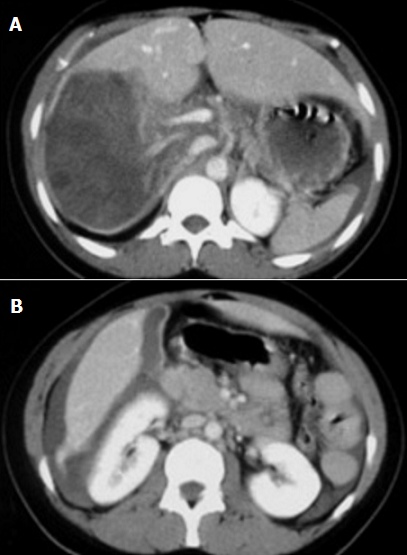

L'hydatidose péritonéale est l'une des complications les plus graves de la maladie hydatique. Elle est favorisée par le siège du kyste, la taille, et la pression intra kystique élevée. La rupture traumatique est le plus souvent iatrogène lors d'une intervention chirurgicale pour Kyste Hydatique du Foie (KHF), nous rapportons une nouvelle observation d'un patient âgé de 26 hospitalisé pour péritonite aigue en rapport avec une rupture d'un Kyste hydatique du foie dans le péritoine.